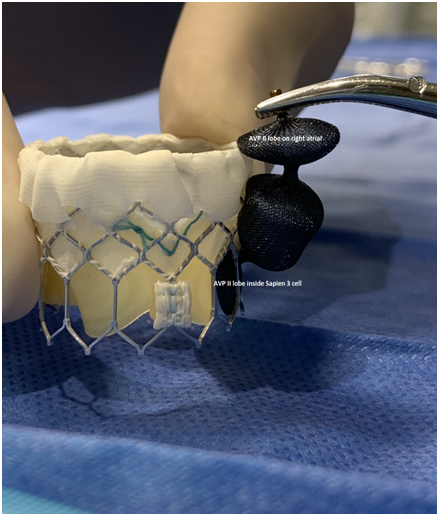

A 73-year-old female with mechanical mitral valve, tricuspid annuloplasty (32mm Edwards Physio Tricuspid incomplete ring) underwent Transcatheter Tricuspid Valve Replacement (TTVR) using off-label 29mm Edwards Sapien 3 (S3) Transcatheter Heart Valve (THV). Immediate post valve deployment, mild Perivalvular Leak (PVL) was noticed at the septal aspect (area of incomplete annuloplasty ring). Eighteen months later, patient presented with recurrent right heart failure and paracentesis due to severe tricuspid PVL (Figure 1A-C, Video 1). Percutaneous PVL closure under general anesthesia, Trans-esophageal Echocardiography (TEE) was performed. Via femoral venous access, defect was easily crossed with Agilis steerable sheath, multipurpose catheter and 0.035” glide wire. Despite recurrent attempts, wire came through the PVL but then traversed through open cells of S3 into the right ventricle (Figure 2A), confirmed with Armada 6mm balloon waist at the S3 cage (Figure 2B) (despite inflating 28mm Z med balloon inside S3 cage, Figure 2C). We decided to partially deploy the plug and assess valve function. Using 7.5F Asahi Eaucath multipurpose guide, a 12mm AmplatzerTM Vascular plug II (AVP II) was advanced through the defect. The ventricular disc was opened inside the S3 cage while body in the PVL defect (outside the S3 cage) and atrial disc on the atrial side of PVL (Figure 3A-B). With S3 function unaffected, no central leak and minimal gradient, PVL reduced to mild severity (Figure 4A-D, Video 2); the AVP II was successfully deployed (Figure 5). At 3-month follow up, there was an excellent symptomatic improvement (NYHA functional class I), with no heart failure re-hospitalization or paracentesis. Deployment of plug disc inside the valve frame is not recommended due to fear of interference with leaflet function and possible injury in long term. There was no immediate issue with the valve function in this case (due to space between the leaflet and frame of S3 and depends on size of plug used). Valve-in-Valve (S3-in-S3) would have certainly sealed all open cells treating this PVL but is more expensive option.

Figure 3 Successful implantation of AmplatzerTM Vascular plug II (white arrows).

Figure 4 Post AmplatzerTM vascular plug II with mild residual PVL (4A), mildly elevated trans-S3 gradient (4B) and normal leaflet mobility of S3 (diastole 4C, Systole 4D).

Figure 5 Amplatzer vascular plug II (AVP II) position in relation to Sapien 3 valve.